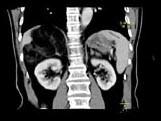

问题 男,59岁,右侧腰背酸痛,CT检查如图所示,应诊断为 ( )

选项 A、右腹膜后脂肪瘤 B、右肾血管平滑肌脂肪瘤 C、右肾上腺转移瘤 D、右肾上腺髓样脂肪瘤 E、右肾上腺腺瘤

答案 D